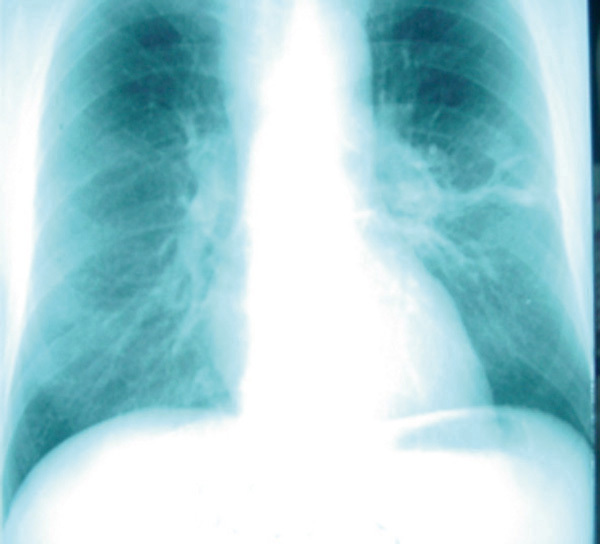

©La Revue du Praticien Radiographie de thorax de face. Syndrome de reconstitution immunitaire au cours d'une tuberculose chez un patient atteint de Sida.